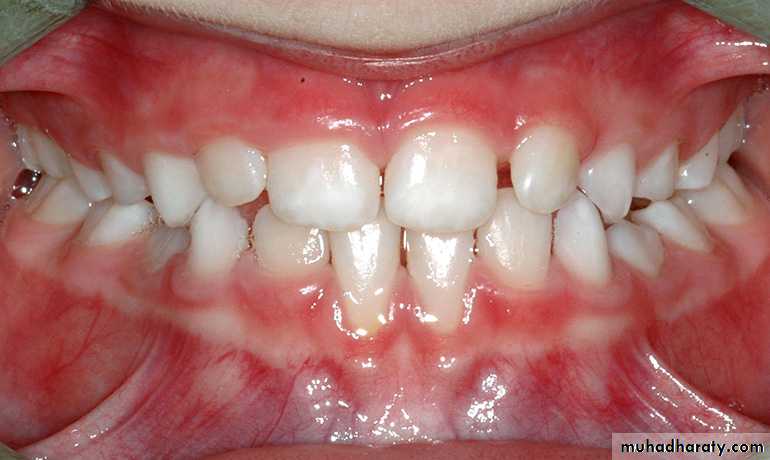

Knowledge of teeth morphology can enable the dentist to identify the teeth when there are multiple extracted teeth , or in period of mixed dentition .• The factors that have been related to the eruption of teeth include:

Sequence of eruption

Primary teeth upper arch ABDCE

lower arch ABDCE

Permanat teeth upper arch 61245378

lower arch 61234578TEETHING AND DIFFICULT ERUPTION